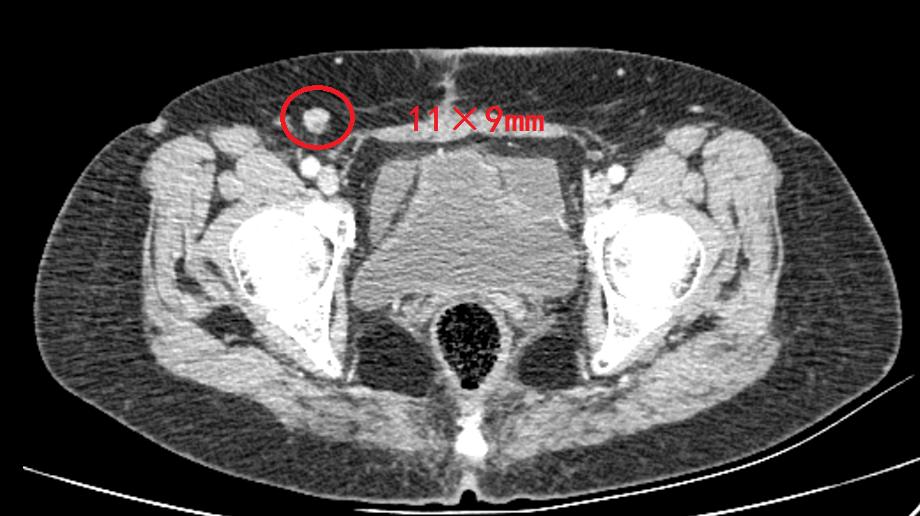

2021-10-25 胸腹部CT示:右肺中叶小结节(伴少许钙化)同前。双侧腹股沟区多发稍大淋巴结。术区结肠壁稍增厚。中腹部脂肪间隙模糊并多发稍大淋巴结(较前相仿):考虑脂膜炎。肝右叶钙化灶。